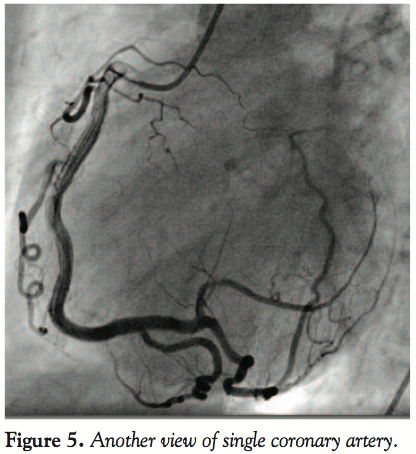

Intracoronary bolus of IIb/IIIa eptifibatide was given and followed by intravenous infusion. Surprisingly, the patient’s hemodynamics were only slightly compromised — she presented with pulmonary congestion (but not pulmonary edema), arterial blood pressure remained normal throughout the angioplasty, and no cardiac support was required (Figures 4, 5, and 6).

On the control angiography, it was apparent that the patient had single coronary vessel that originated in the right sinus of Valsalva. The LM ostium was absent. The single artery showed a typical course of a dominant RCA and created branches to the circumflex artery (LCX) and the left anterior descending (LAD) branch. The secondary vessels clearly branched toward the base of the heart and they showed no significant arteriosclerotic lesions. Echocardiography found no concomittant

Our case may be classified as an SCA. It is type IIA of single coronary ostium according to a recent classification by Shirani and Roberts. There are approximately 20 subtypes of SCA. It is a very rare condition, with an incidence of 0.03%. Type IIA differs significantly from other variations, since there is a single coronary trunk and it does not immediately divide into left and right system. This is a “true” SCA that gives away its branches on its way toward the base of the heart. This variant should be distinguished from another congenital anomaly, namely LM atresia/agenesis. In single RCA, all branches create one functional and anatomical system, while in LM atresia there are two systems that are connected by clear collateral circulation from right to the left via conus branch artery (Vieussens’ anastomoses), anterior ventricular branches of RCA, or branches supplying the LAD through the right posterior descending artery (PDA).10 LM atresia usually demonstrates significant clinical consequences, while single RCA does not.11 LM atresia/agenesis is extremely rare, and is usually diagnosed in early childhood in very sick patients who present with myocardial infarction, syncope, or failure to thrive. In older patients, symptoms such as dyspnea and angina appear when collaterals prove unable to cope with growing heart demands. Untreated LM atresia leads to serious consequences in both groups, with many patients dying suddenly. However, when treated (most often with surgical reconstruction of LM or bypass surgery), they fare well.12 Atherosclerotic occlusion of LM artery is another condition that portends a poor outcome and needs to be distinguished from single RCA.13 The prognosis in coronary artery anomalies is unclear. According to Van Camp et al, they may be responsible for 11.8% of deaths among United States school and college athletes. In the Sudden Death Committee of the American Heart Association, this figure is even higher, reaching 19%. In the literature, the incidence of coronary artery anomaly is approximately 1%.1 Angelini et al found a much higher value of 5.6% based on 1950 angiograms.23 In an American Armed Forces Institute database of 6.3 million 18-year-old recruits who were subjected to strenuous exercise during their training, there were 277 deaths not attributed to trauma. Cardiac cause was found in 64 individuals, of which 21 (33%) were due to left coronary artery anomaly originating from the opposite sinus. No other coronary artery anomaly could have been linked to their deaths. SCA seems to confer good prognosis unless one of its branches has interarterial course (ie, the artery lies between the aorta and pulmonary trunk). The latter variant is associated with poor prognosis, but the mechanism remains unclear. The proposed explanations are: compression of the aberrant artery between main arteries during strenuous exercise, intramural course of the coronary artery in the aorta, and smaller cross-sectional area of the affected artery.14